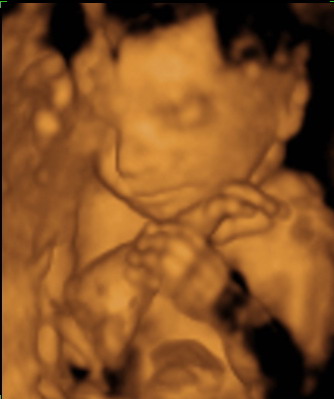

POcak fotó: mi itthon csináltunk, az is tökjó lett. Én ugye lenni kisbálna, így nem akartam volna művészi képeket csinálni magamról... Most se kívánkozik

Igaz Alex pocakról nincsen annyi képem, mint Hannáról... most valahogy Hanna és a meló elvitte azt a maradék erőmet is, hogy a képeket megcsináltassam Ádámmal. Szimplán nem jutott eszembe.